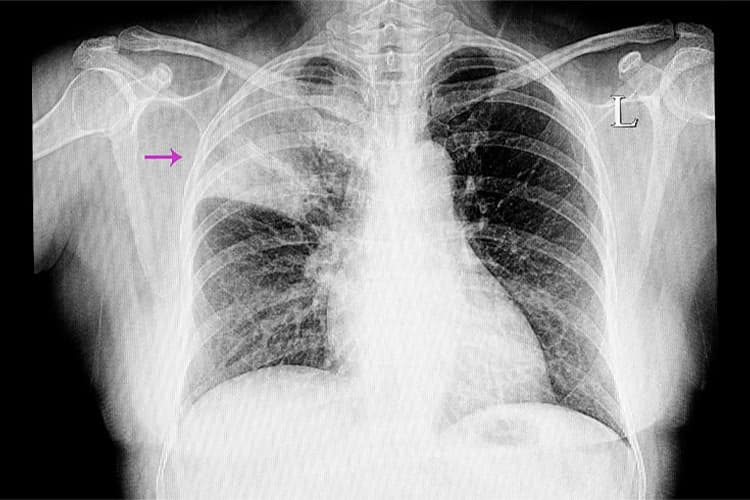

• レントゲン検査で肺炎像を確認します。CTを検討するケースについては連携医療機関に紹介させていただきます。